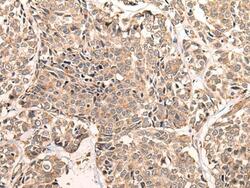

- Immunohistochemistry of paraffin-embedded Human liver cancer tissue using LDAH Polyclonal Antibody at dilution of 1:55(×200)